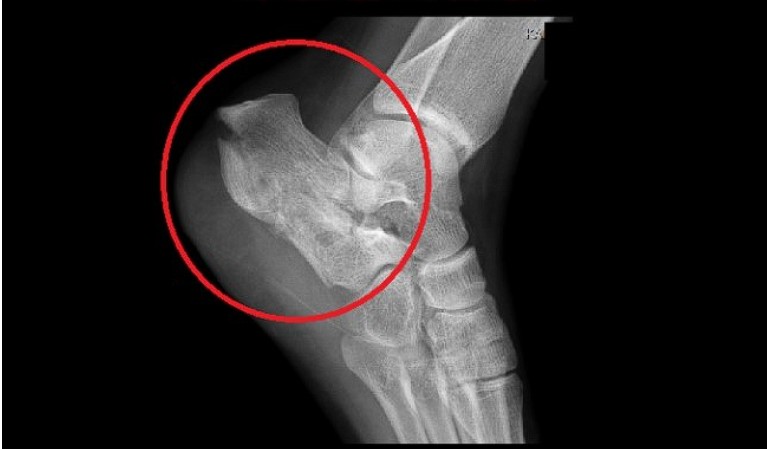

8. 발바닥에 딱딱한 결절

일부 환자들은 발꿈치에 결절이 생길 수 있습니다. 결절은 발꿈치 뼈에 작은 돌출부위로, 족저 근막염이 장기화되면 나타날 수 있습니다. 이 결절은 발꿈치를 눌렀을 때 통증을 유발합니다.